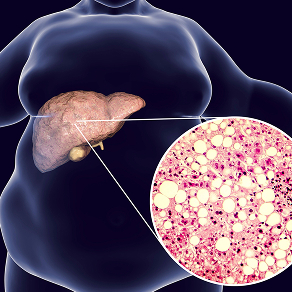

Lambda Biologics provides state-of-the-art organoid-based disease modeling and drug evaluation services. Utilizing human induced pluripotent stem cells (iPSCs), our platform generates three-dimensional organoids that accurately recapitulate organ structure and function. This enables precise modeling of disease mechanisms and predictive assessment of therapeutic compounds.

Organoids mimic human tissue architecture and cellular heterogeneity, providing more translationally relevant data than traditional 2D cultures or animal models.